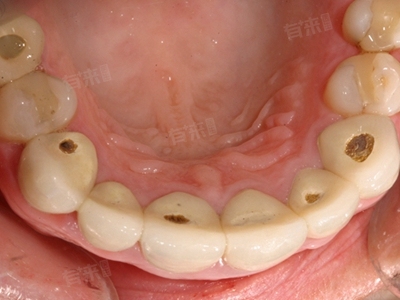

牙齿有洞一般是指龋洞,是牙体硬组织在细菌、饮食、宿主因素及时间共同作用下发生的慢性破坏。常见原因包括细菌及牙菌斑作用、高糖及酸性饮食、牙齿结构缺陷等。

1、细菌及牙菌斑作用:龋齿的主要致病菌是变形链球菌、乳酸杆菌等产酸菌。它们附着于牙面形成牙菌斑,分解食物中的糖类产生酸性物质(如乳酸),使牙釉质脱矿,长期作用形成龋洞。若不及时清除菌斑,龋坏可向深层牙本质发展,甚至累及牙髓。

3、牙齿结构缺陷:牙釉质发育不全、矿化不良或牙列不齐(如拥挤牙、深窝沟)会增加食物残渣滞留,难以清洁,使局部更易堆积菌斑。儿童乳牙及年轻恒牙因釉质较薄弱,龋齿进展更快。

5、口腔清洁不足:不规范的刷牙习惯、未使用牙线或间隙刷清洁邻面,导致菌斑长期堆积。此外,忽视定期口腔检查,早期龋未能及时干预,龋洞逐渐扩大。